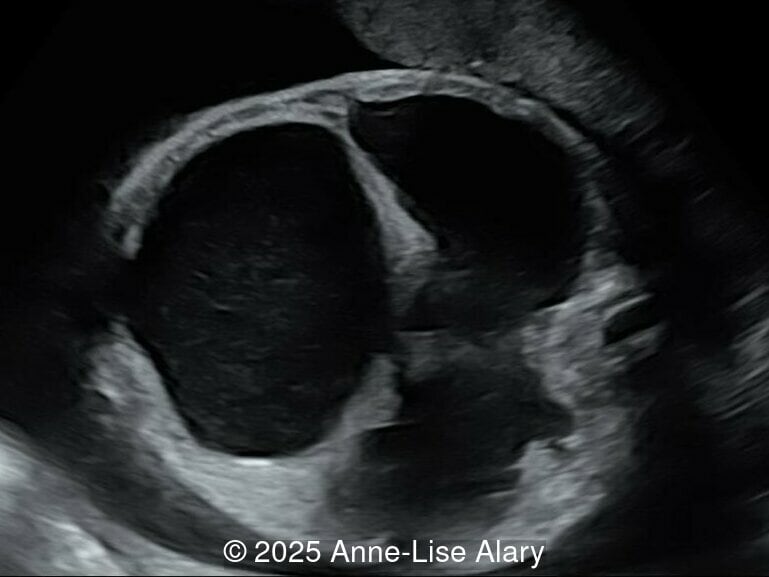

Image 2

Axial image of the abdomen

Image 3 Axial image of the abdomen

Our prenatal ultrasound revealed a male fetus with megabladder, dilation of both ureter and kidneys, and thinned kidney parenchyma consistent with Lower Urinary Tract Obstruction (LUTO).  Additional findings suspected on ultrasound and confirmed on computed tomography included:

The diagnosis of PBS is often made in the second trimester of pregnancy, although it has been described as early as 11 weeks of gestation [20]. The most frequent ultrasound findings are a large, thin-walled bladder accompanied by bilateral hydroureter/hydronephrosis, dysplastic kidneys with echogenic renal parenchyma and renal cortical cysts, and abdominal wall laxity which is better viewed after bladder decompression [21]. Cryptorchidism can be detected prenatally by 28 to 30 weeks gestation when the testes descend into scrotum. There may be a patent urachus, visible as a cystic connection between bladder and umbilicus. Oligohydramnios is a frequent finding, which makes it difficult to visualize the associated anomalies.